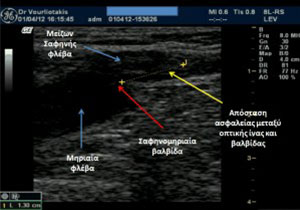

Η θεραπεία των κιρσών με ενδοφλέβιο Laser* είναι μία σχεδόν αναίμακτη επέμβαση που πραγματοποιείται με τοπική αναισθησία, υπό υπερηχογραφική καθοδήγηση, με ασφάλεια και ακρίβεια. Από την περιοχή της κνήμης εισάγεται διαδερμικά στη σαφηνή φλέβα η οπτική ίνα του Laser, η οποία προωθείται κεντρικά ως το ύψος της σαφηνομηριαίας συμβολής. Καθώς η οπτική ίνα αποσύρεται προοδευτικά, διαχέει ακτινικά ενέργεια, η οποία συρικνώνει ομοιογενώς τα φλεβικά τοιχώματα και σφραγίζει πλήρως τη φλέβα. Μετά το κλείσιμο της πάσχουσας φλέβας η κυκλοφορία αποκαθίσταται μέσα από τις υγιείς φλέβες του δικτύου.